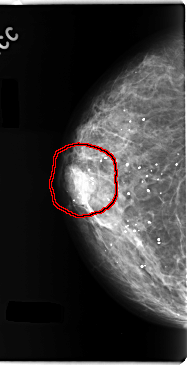

C_0145_1.RIGHT_CC

FILE: C_0145_1.LEFT_CC.OVERLAY

TOTAL_ABNORMALITIES 1

ABNORMALITY 1

LESION_TYPE MASS SHAPE LOBULATED MARGINS CIRCUMSCRIBED

ASSESSMENT 5

SUBTLETY 5

PATHOLOGY MALIGNANT

TOTAL_OUTLINES 1

BOUNDARY